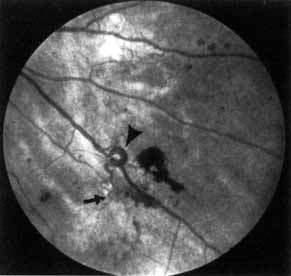

As demonstrated by increased latency and decreased amplitude of the visual evoked potential, many patients with diabetes without retinopathy have subclinical optic neuropathy.269,270 In addition, patients with diabetes can develop two types of acute optic neuropathy. The first, anterior ischemic optic neuropathy (AION) is identical to that seen in patients without diabetes. The patients report a sudden decrease in visual acuity or a sudden visual field loss.271–273 The main ocular finding is a “pale swelling” of the optic nerve head with, considering the degree of disc edema, very few hemorrhages (Fig. 27). On fluorescein angiography segmental nonfilling or slow filling is seen (Fig. 27). An afferent pupillary defect (Marcus Gunn) is nearly always present. Visual fields commonly show altitudinal or nerve fiber bundle defects. The disc progresses to optic atrophy (Fig. 27), and improvement in visual function is rare.

Fig. 27 A. Right eye: ischemic optic neuritis. Note pale swelling of optic disc and blurring of disc margins. Left eye: normal disc. B. Fluorescein angiogram. Note poor filling on disc inferotemporally as compared with the rest of the disc. C. Right eye 6 months after optic neuritis. Note slight pallor.